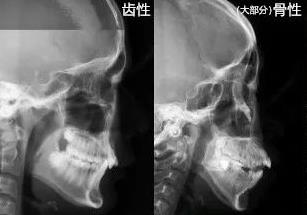

齙牙有牙性和骨性之分沒錯,牙性,就是牙齒的問題造成的,骨性就是骨頭造成的,還有的兩(liang) 者的原因都有,不過需要看占比多少。性質不同,治療方案不同,方法不同,結果也有差異。

有一種說法是,骨性的齙牙,除了牙齒突出之外,上頜骨和鼻子周圍是鼓起的,而且還有下巴短小、後縮的表現;而牙性齙牙通常隻是牙齒前突,上嘴唇和鼻子周圍不是鼓的。這是可以判斷的,但是沒法判斷具體(ti) 占比多少,所以還是找正規醫院和醫生檢查測量綜合分析更準確。

而且牙性和骨性結合的**通常會(hui) 比較多,占比不同,方案差異也較大。如果是牙性的,那麽(me) 通過單純正畸,拔牙戴牙套矯正,得到的結果是比較理想的,能較大程度改善側(ce) 麵形象;如果是骨性的,單純正畸改善不大,需要手術矯正的幾率更高一些。